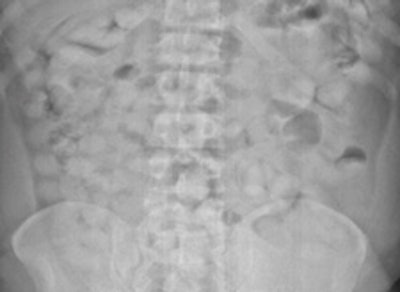

Top left: Low-dose linear slit digital radiography (LSDR) of a typical body packer with 145 intracorporal packs along the alimentary tract. Bottom left: Magnified view of the packs. Note the radiolucent rim within the periphery of the packs due to air trapping creating the so-called "double-condom sign" and "halo sign." Top right: DR of a typical body packer with 83 cocaine packs in the gastrointestinal tract. Bottom right: Note the longitudinal packs (weight approximately 10 to 12 g) projecting over the colon. The magnified view depicts the typical "double-condom sign" due to inevitable air trapped within the wrapping layers during manufacture.DR and low-dose linear slit digital radiography exams were less accurate. CT exams had an overall accuracy rate of 97.1%, followed by DR (71.4%, and 60% for low-dose linear slit digital radiography).